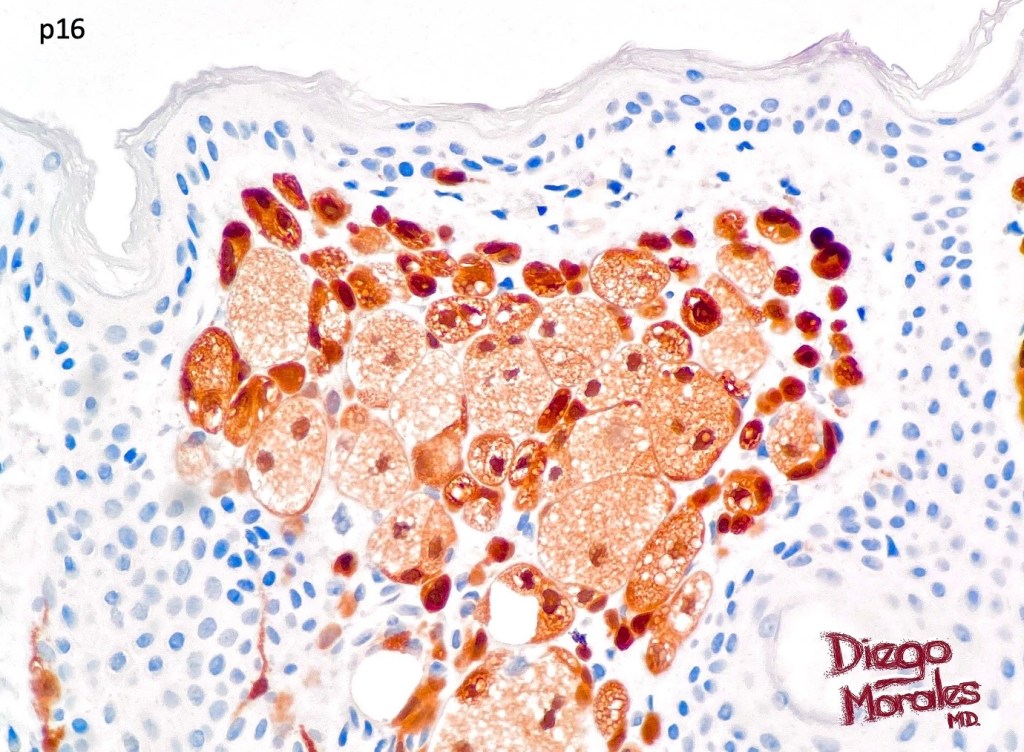

. In some balloon cell nevi, the microvesicles may result in nuclear scalloping reminiscent of a sebaceous tumor. In cases where there is real doubt, immunohistochemistry (S100), SOX10) will resolve the problem.

The importance of the entity is that it must always be distinguished from balloon cell melanoma. All cases should be scrutinized very carefully for pleomorphism and mitotic activiy before rendering a diagnosis of balloon cell nevus.